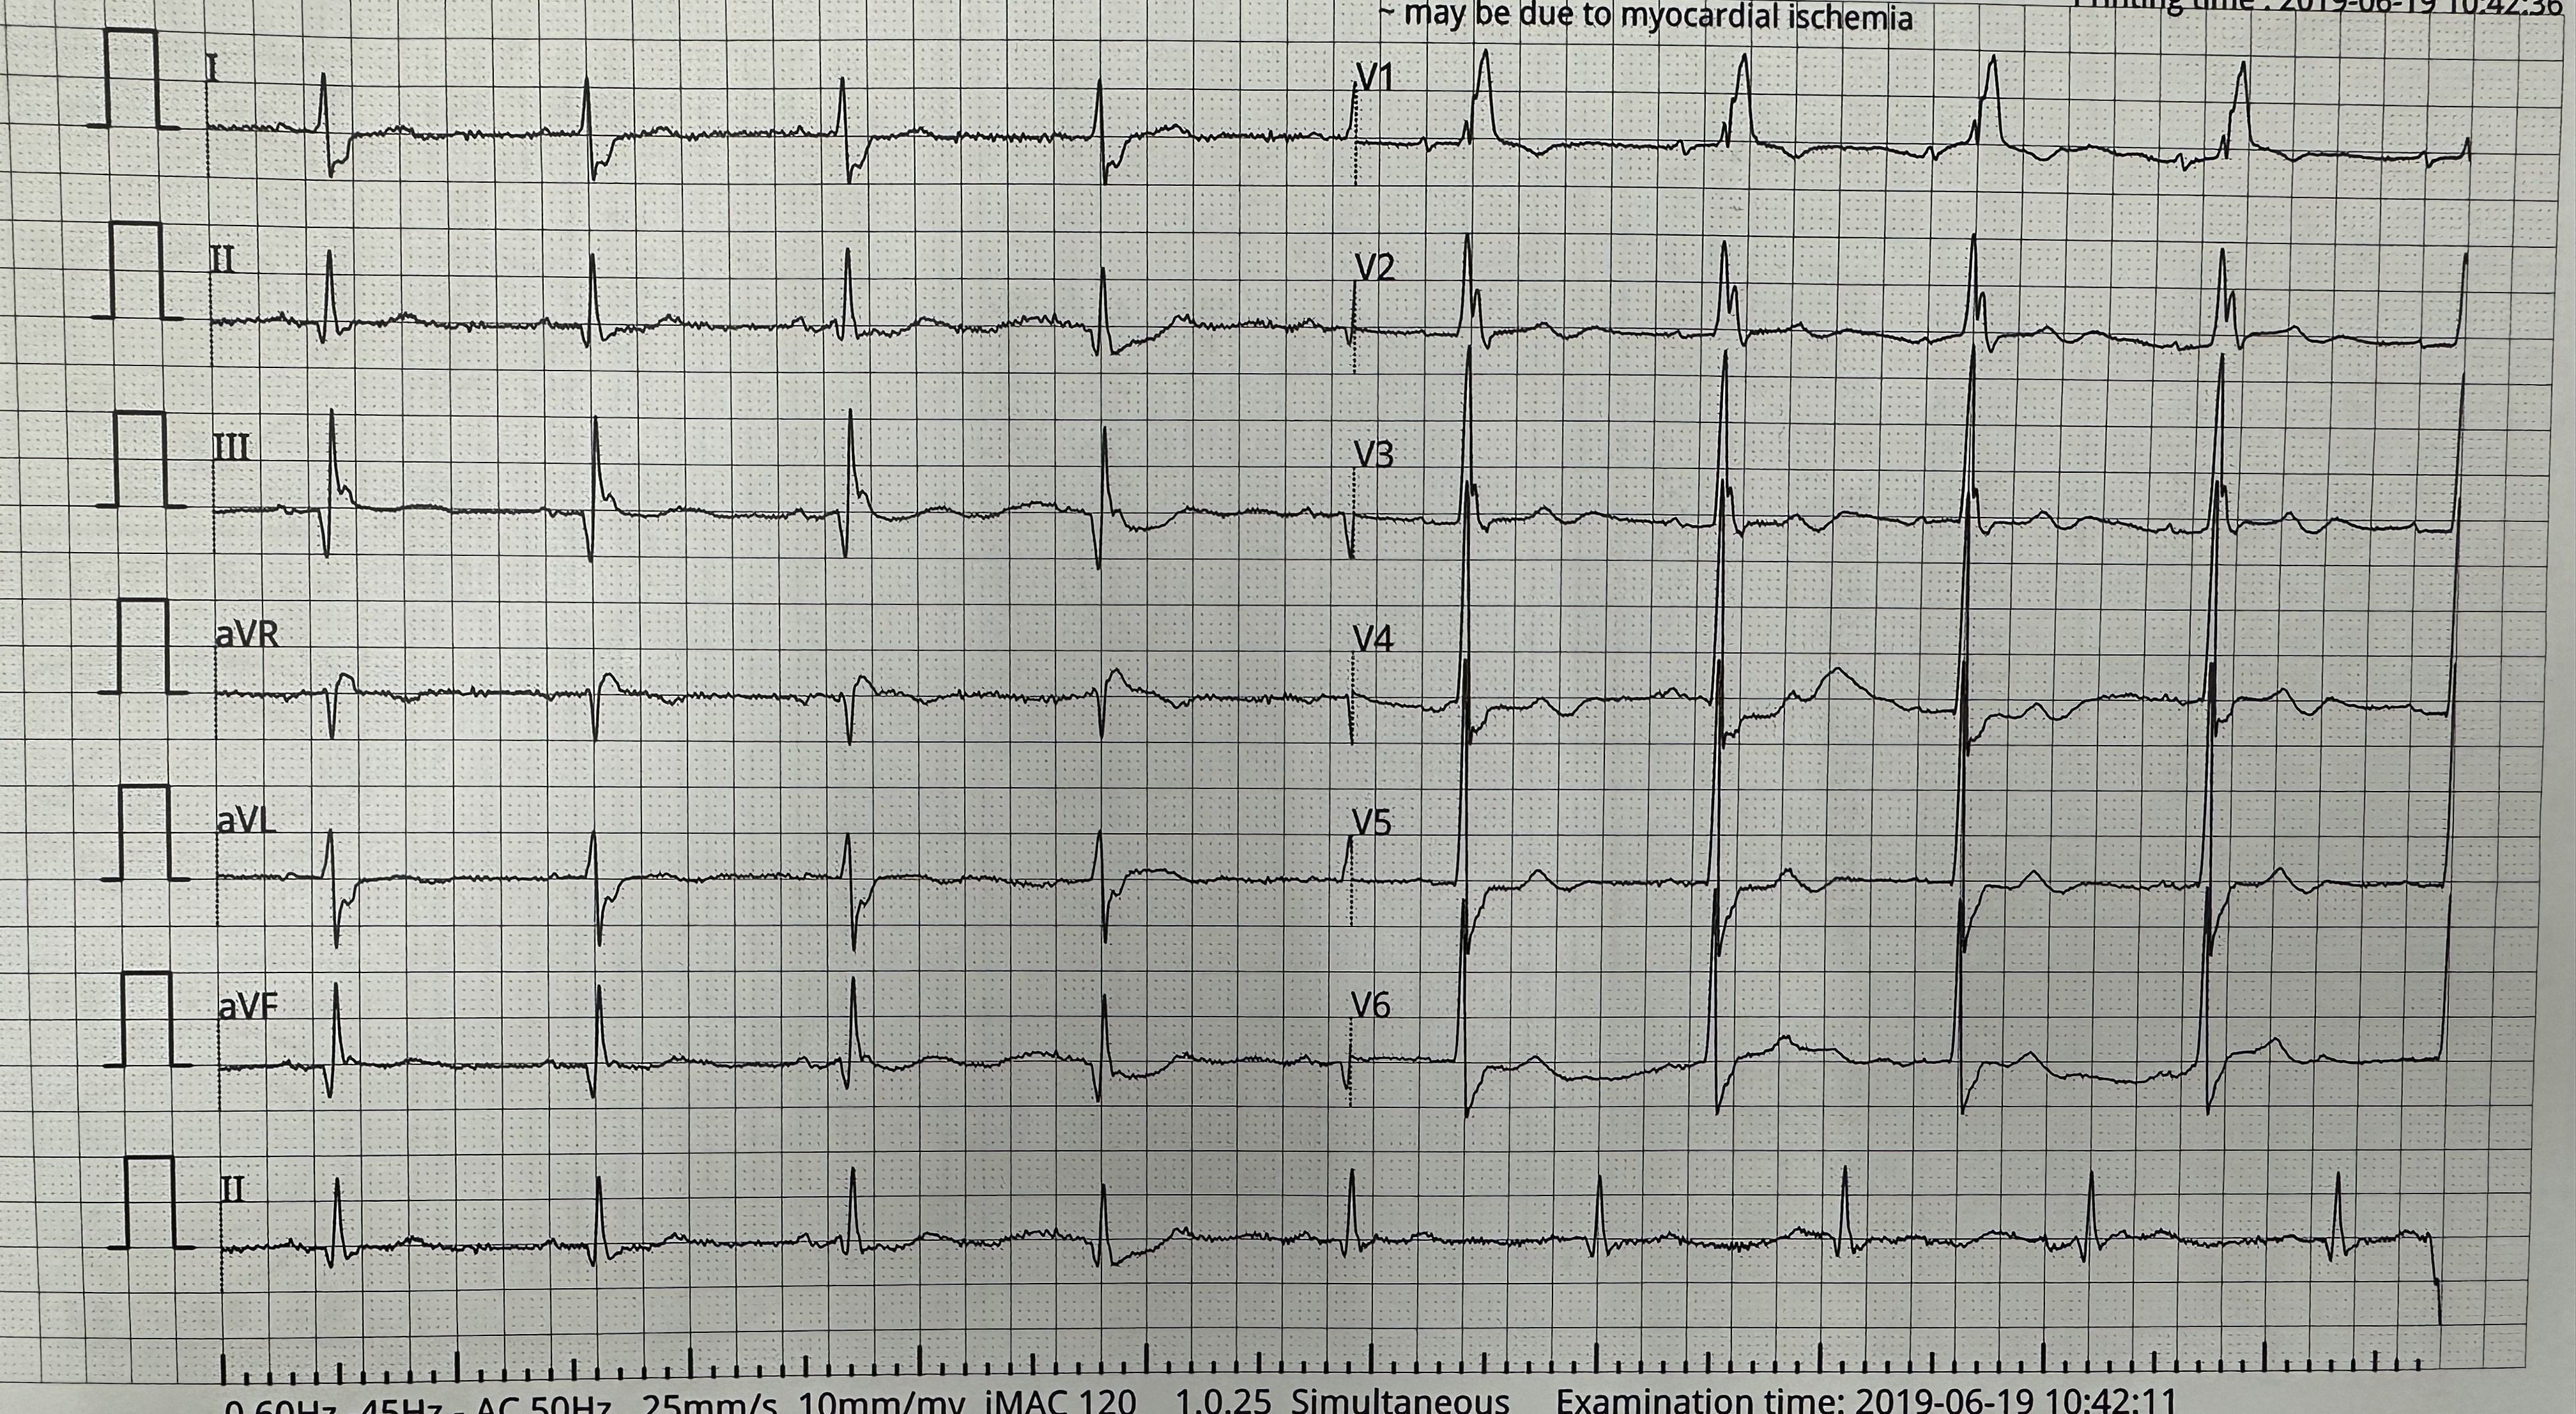

Relevant Test Results Prior to Catheterization

ECG showed sinus rhythm with right bundle branch block , Qwave over inferior lead ( lead 2,3 and AVF). Echocardiography showed left ventricular ejection fraction of 35%, global hypokinesia and dilated left ventricular and atrial chamber.